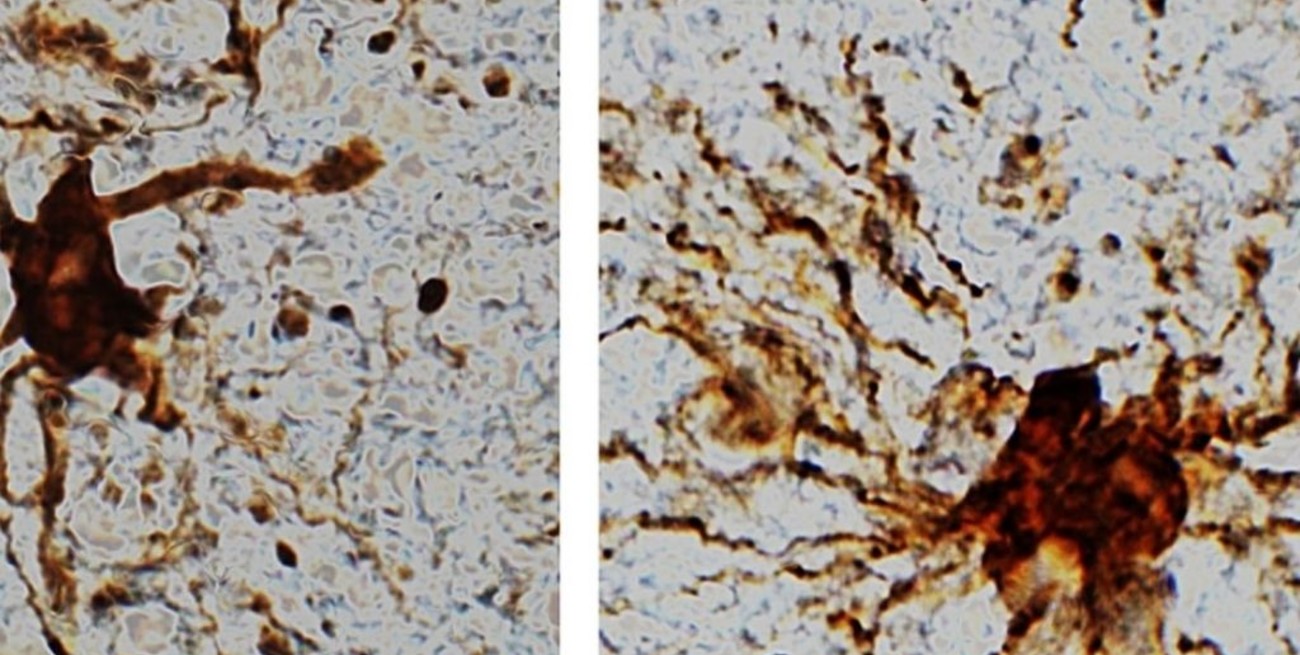

El descubrimiento fue posible gracias al análisis de la expresión génica del tejido encefálico recolectado de pacientes durante cirugías rutinarias. Establecieron que cerca del 80% de los genes se mantienen relativamente estables durante 24 horas, mientras que los asociados con neuronas se degradan en las primeras horas 'post mortem'.